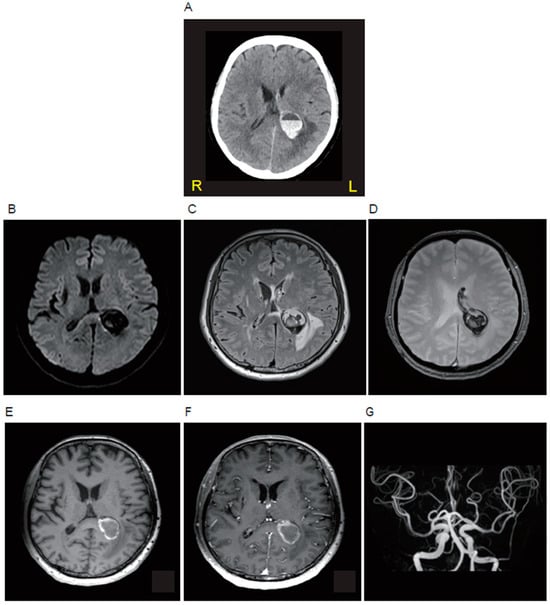

A 57-year-old woman presented at our hospital with a complaint of fever and headache lasting for several days. She had a history of embolic stroke of an undetermined source and took warfarin (4.25 mg/day). Her body temperature was 37.7 °C. The neurological examinations revealed alert consciousness and mild hearing loss in the left ear, with no other neurological abnormalities such as meningeal irritation signs and motor palsy. Blood tests showed an elevated white blood cell count of 5, 180/μL, CRP 0.04 mg/dL and PT-INR 2.89. The head non-contrast computed tomography (CT) showed a circular hemorrhagic lesion with an air-fluid level inside at the left hemisphere, attaching to the left ventricle (Figure 1A). Brain magnetic resonance imaging (MRI) showed a hypointense round lesion on diffusion-weighted imaging (Figure 1B), a cystic lesion with heterogeneous hypo- and hyper-intensities on fluid-attenuated inversion recovery imaging (Figure 1C) and T2*-weighted imaging (Figure 1D), a lesion wall with hyperintensity on T1-weighted imaging (Figure 1E), and the enhancement of the wall on contrast enhancement T1-weighted imaging (Figure 1F). MR angiography (Figure 1G), as well as conventional cerebral angiography, showed no abnormal vessels or aneurysms. A CSF examination showed that the cell count was mildly elevated (23/μL; polynuclear cells 5/μL: mononuclear cells 18/μL), and the protein level was also elevated (125 mg/dL), but the glucose level was decreased (51 mg/dL; blood glucose of 128 mg/dL examined at the same time). According to the findings indicated above, a brain abscess accompanied by intracerebral hemorrhage was clinically suspected.

Figure 1. Neuroradiological findings of the patient in the acute phase. The brain lesion is shown by brain computed tomography (A), diffusion-weighted magnetic resonance imaging (MRI) (B), fluid-attenuated inversion recovery MRI (C), T2*-weighted MRI (D), T1-weighted MRI (E), contrast-enhanced T1-weighted MRI (F), and MR angiography (G).

An intracerebral hemorrhage accompanied by a brain abscess was clinically suspected in this case. Intracerebral hemorrhages are rarely involved in brain abscesses. The mechanism of a hemorrhage in the brain abscess is still unclear, but neoangiogenesis observed in brain abscesses was demonstrated by the increased expression of vascular endothelial growth factor and microvascular density [28]. The neoangiogenesis in the wall of the brain abscesses is susceptible to the rupture of newly formed fragile blood vessels [29]. In our case, contrast-enhanced T1-weighted imaging revealed an enhanced abscess wall, suggesting the presence of neovascularization in the wall. Furthermore, the patient was taking warfarin, which could contribute to the bleeding tendency.